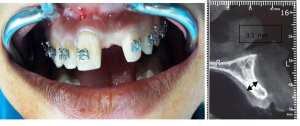

A 19-year-old female patient presented with a missing maxillary left central incisor (tooth number 21); the medical history was noncontributory. The width of the alveolar crest was 3.1mm, which could not allow for any implant insertion (Figure 1 and 2).

Figure 1 and 2: Photo showing the volume loss in the buccal side and cross-sectional image measuring the bucco-lingual thickening of residual bone